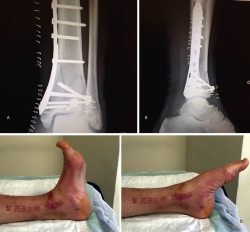

Figura 17. Caso 3: fractura tipo C. Radiografías sin tracción y con tracción comprobando la reducción.

Figura 18. La tomografía computarizada muestra los fragmentos principales de la fractura, estando desplazado el Tillaux que se reduce con la tracción.

Figura 20. Radiografías postoperatorias y resultado final con movilidad completa en flexoextensión del tobillo.